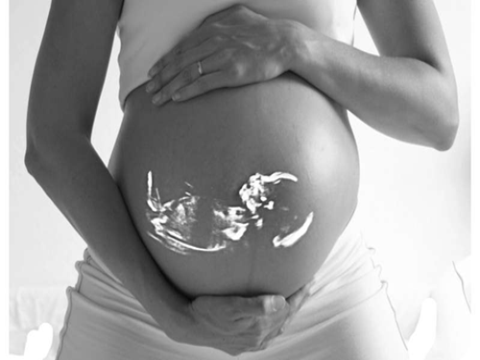

Liệu pháp tế bào gốc trong tử cung đầu tiên để điều trị tật nứt đốt sống ở thai nhi cho thấy kết quả an toàn